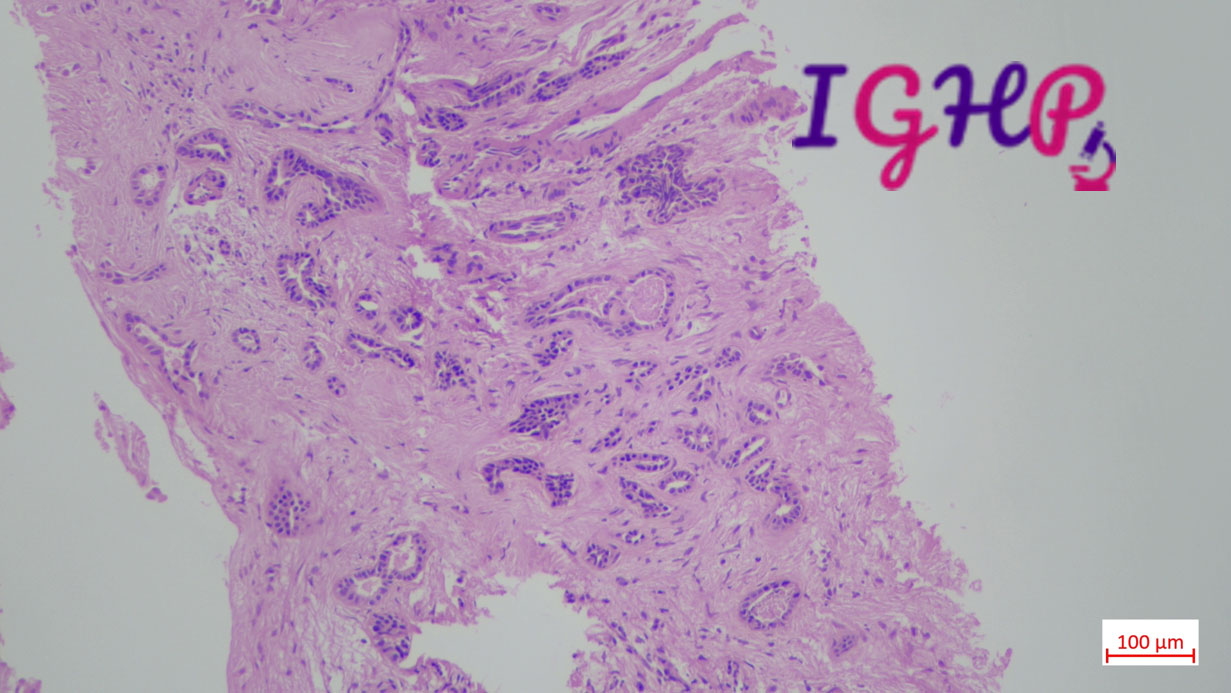

Microscopic Images-

Microscopic examination showed atypical bile ductular proliferation in dense sclerotic stroma. Areas of mild nuclear pleomorphism noted. Intraluminal apoptotic debris seen.